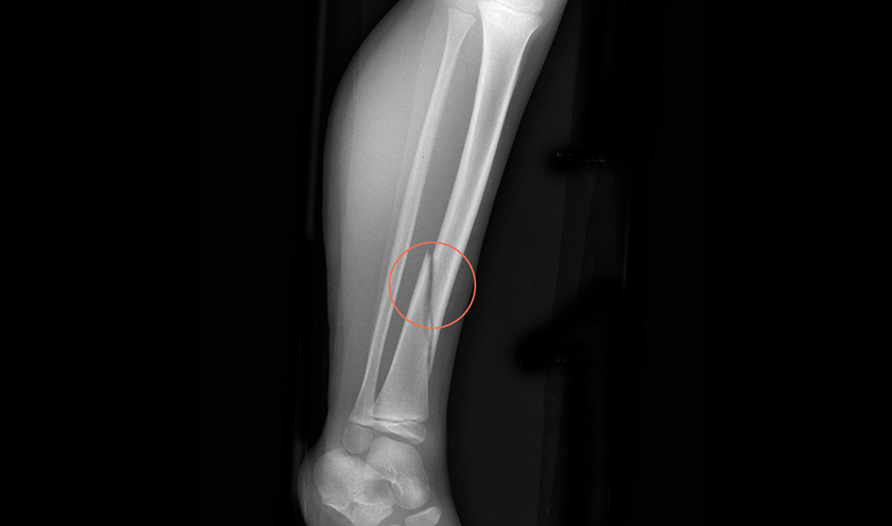

Rbfracture™

AI-powered, automatic detection of trauma-related findings

Hip fractures are the most common disabling injury and cause of accidental death in older people.

It is estimated that between 2-9% of hip fracture cases are missed

Trial showing improved diagnostic accuracy for Emergency Care residents when

reviewing hip fracture X-rays

5.6%

Average improvement in

Sensitivity when using the tool